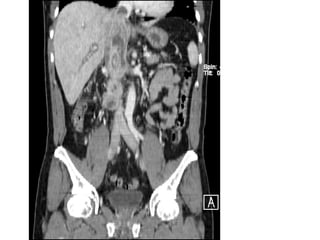

ASCITE